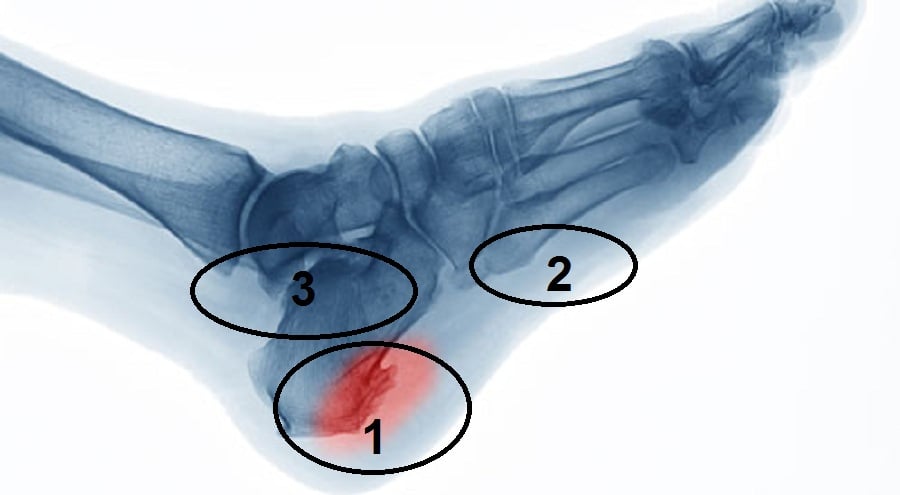

من زمان علمونا غلط.. مناطق الالم الاشهر في الصوره من 1 -2- 3

ت2